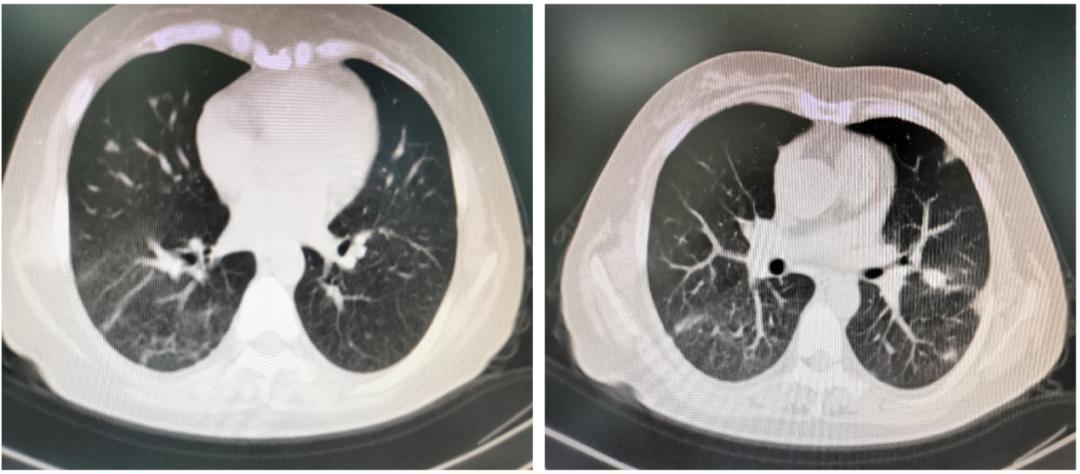

到2021年5月,对患者使用的醋酸泼尼松已减量为20mg qd维持治疗, 复查胸部可见双肺多发高密度影较前明显缩小(图4),且病情无反复。

图4. 复查胸部CT可见双肺多发高密度影较前明显缩小